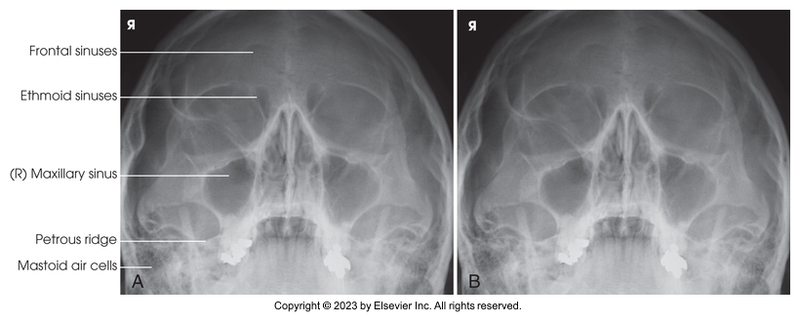

Parietoacanthial projection of the maxillary sinuses - Waters Method

Parietoacanthial of the maxillary sinuses (Waters Method)

Parietoacanthial of the maxillary and sphenoidal sinuses (Open-mouth waters method)